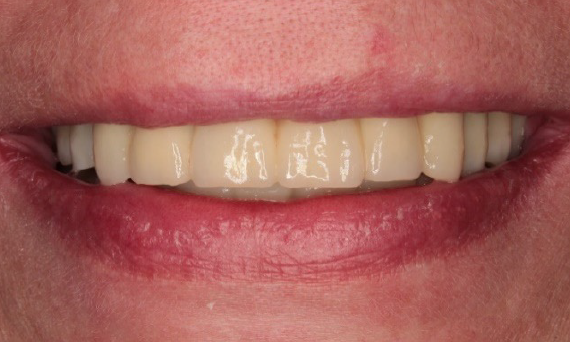

Exzellente Ästhetik

Langfristiger marginaler Knochenerhalt für eine exzellente Ästhetik über Jahre hinweg. Sie wissen, dass Sie gewonnen haben, wenn Ihr anspruchsvollster Patient dauerhaft zufrieden ist.

Langfristiger Knochenerhalt und exzellente Ästhetik dokumentiert und klinisch erprobt.

Die Hauptmerkmale des Implantats – EV-Innenverbindung, OsseoSpeed, MicroThread, Soft Tissue Chamber – wurden für das Astra Tech Implant System hinsichtlich Knochenerhalt und Ästhetik dokumentiert und klinisch erprobt.

SoftTissue Chamber – größeres Weichgewebevolumen und hohe Ästhetik